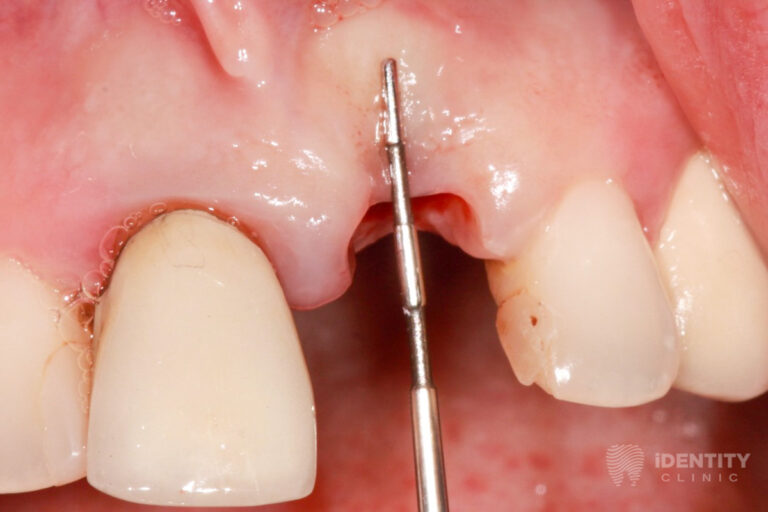

Bal felső első foga nagymértékben mozogni kezdett, ínye gyakran vérzik fogmosás közben.

A páciens krónikus fogágybetegségben (közismertebb nevén fogínysorvadásban) szenved. A gyulladás következtében kisebb-nagyobb mértékben elpusztult a fogak tartószerkezetét jelentő csont a fogak körül.

A bal felső első fog körül már olyan nagy mértékű a csonthiány, hogy a fogat reménytelen prognózisa miatt eltávolításra ítéltük. A többi, szintén parodontalisan (fogágybetegség által) érintett fog teljeskörű parodontalis terápiájának megkezdése indokolt.

A bal felső első fog eltávolításával egyidőben csontpótlást (alveolus prezercációt) végeztünk. A sebészi beavatkozás lényege, hogy a fogeltávolítást követően az alveolus (az eltávolított fog helye a csontban) ne essen össze a nagymértékű csonthiány miatt, hanem azt fenntartva a páciens saját csontját és kötőszövetét felhasználva megőrizzük a csontkontúr eredeti formáját.